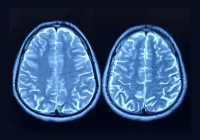

Clinical reasoning, especially in radiology, heavily relies on identifying and interpreting cues from medical imaging. Radiologists use a process known as cue utilisation, which involves recognising patterns and cues that are not always apparent to novices. This expertise allows radiologists to quickly and accurately assess medical images by focusing on clinically relevant features, such as nodule brightness or specific symptoms. The ability to utilise these cues efficiently is a hallmark of expertise in the field, enabling radiologists to form a "clinical gestalt" or an intuitive understanding of a medical situation based on experience and environmental context.

Integrating artificial intelligence (AI) in medical diagnostics, particularly in radiology, promises to revolutionise clinical decision-making. However, the pace at which AI technologies are being developed and commercialised significantly outstrips our understanding of their practical value for clinicians. This rapid development has created an "AI chasm," a gap between technological advancements and their effective application in clinical settings. This article explores the cognitive aspects of clinician decision-making, the differences between human and AI processes, and the implications for the future of medical AI.